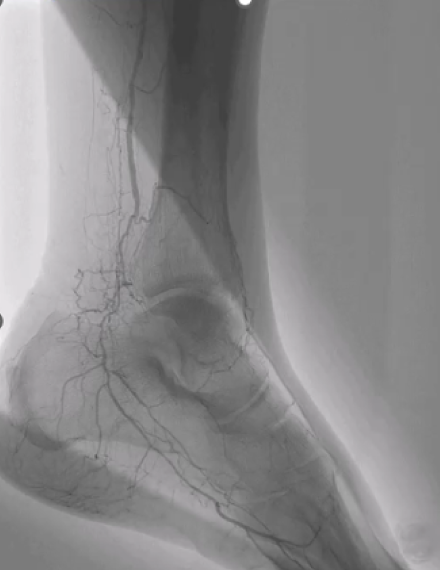

Pre-procedure

Image shows poor distal run-off at the dorsalis pedis artery. -